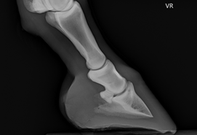

- Bildgebung (Ultraschall / Röntgen)

- Sportpferdemedizin

Wir bieten moderne Diagnostik und umfassende Behandlungsmöglichkeiten für Ihr Pferd und können ein sehr breites Leistungsspektrum anbieten. Mobil bei Ihnen im Stall oder stationär.